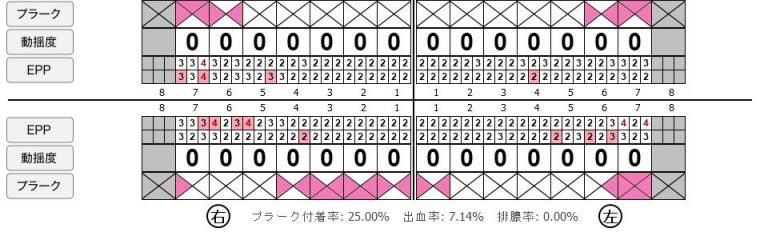

症例1

Before

after

Before

after

基本情報

| 年齢・性別 | 52歳・男性 |

|---|---|

| 主訴 | 主訴:久しぶりの歯医者なので歯石をとってほしい 治療部位:全顎 |

| 治療内容 | 1.歯磨き指導、歯肉縁上の歯石除去 2.歯磨きの確認、指導(磨けるようになるまで) 3.歯磨きの確認、指導、歯肉縁下の歯石除去(SRP) 4.PMTC 5.再評価、歯磨きの確認、指導 |

| 治療期間 | 1日 |

| 治療費 | 合計17,560円 ・内訳 1、歯周基本検査・歯磨き指導、縁上スケーリング:1,800円 2、歯周精密検査・SRP(スケーリング・ルートプレーニング)、歯磨き指導:2,130円 3、SRP、歯磨き指導:3回(1,530円×3回) 4、PMTC、全顎再スケーリング、歯磨き指導:5,500円(自費診療)+1,260円 5、再評価(歯周精密検査)、歯磨き指導:2,280円 ※PMTC以外、保険診療3割負担 (2023年5月現在現在) |

| リスク・副作用 | ・毎日の歯磨きが不十分だと歯石を除去しても再度歯石がついてしまう ・最初は歯磨きのときに出血してくることがあるが、細菌が減って歯茎が引き締まってくると徐々に出血は落ち着いてくるため痛みがなければ辛抱強く磨いてもらう ・歯周病は時間をかけて静かに進行する病気なので、歯周病を治すにはそれなりに期間がかかる、すぐには治らない ・歯ぐきが引き締まると歯茎が下がり歯間に隙間ができる可能性がある |

| 治療方針 | 一時的な治癒ではなく、将来的にこの治療が活かされるよう、患者さん自身である程度自己管理ができるようになることを目標とした |

| 特記事項 | ふつうのブラシと電動歯ブラシ使用(ブラウン丸型使) 歯間ブラシを1日1回は最低でも使って頂いた |

| 担当者所見 | あまり器用な方ではなかったため、決まったところがいつも磨けず奥歯に歯間ブラシがなかなか入れられませんでしたが、歯間ブラシのサイズを変えてみたり、内側から入れてみたりと試行錯誤してなんとかある程度磨けるようになりました。 その結果、出血が100%から7%へ激減することができました。 ただSRPをしただけではここまでの結果は出なかったと思います。 それほど日々のセルフケアが重要だということを再認識しました。 歯周ポケットが残っている部位、出血がある部位に関しては引き続き歯磨きを念入りに行なってもらう。 |